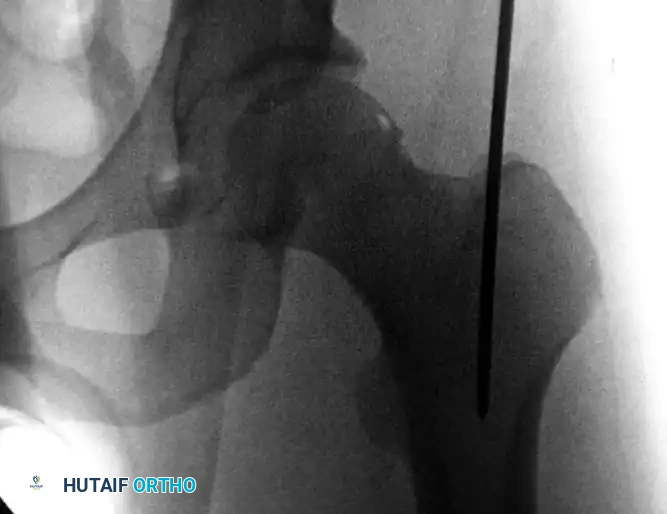

Establishing the Entry Portal

Advance a threaded-tip guidewire to the chosen entry point. If utilizing a trochanteric antegrade technique, the entry point must be precisely on the medial slope of the greater trochanter to avoid iatrogenic varus malalignment.

Image

Trochanteric starting portal for antegrade intramedullary nailing procedures of the femur. Note the trajectory aligning with the anatomical axis of the medullary canal.

Image the trochanteric region in both AP and lateral planes. The guidewire trajectory must permit central placement into the medullary canal distally. If the pin is slightly eccentric, a soft-tissue guide with a multiple-pin "honeycomb" insert can be utilized. This allows the surgeon to place a second, perfectly positioned pin parallel to the first without losing the initial reference point. Once perfect positioning is confirmed, advance the guidewire distal to the lesser trochanter.